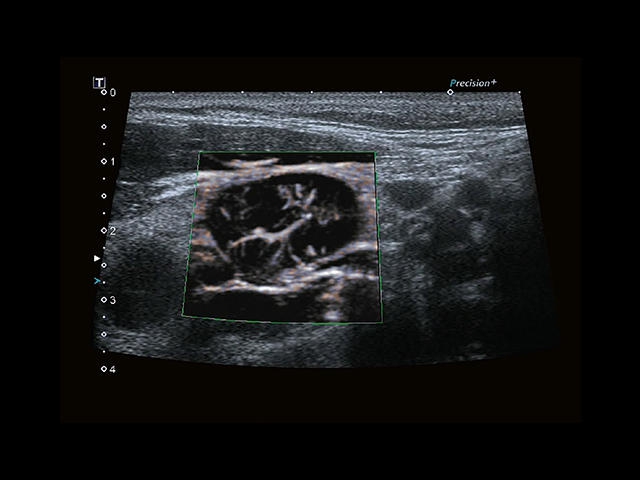

Обновленная версия легендарного УЗ-сканера. Стационарный аппарат экспертного класса Aplio 500 Toshiba NEW, визуализирует анатомические структуры в высоком разрешении. Модель позволяет выявить микрокальцификаты, новообразования, нарушения в работе сердца, сосудов и мышц. Присутствует функция виртуальной эндоскопии, 4D-сканирования, эластометрии тканей, УЗИ с контрастированием. За повышение качества изображения отвечают технологии ApliPure и Superb Microvascular Imaging. Первая задействует возможности пространственного и частотного кодирования, формирует цельный визуальный ряд с сохранением клинических маркеров. Вторая улучшает отображение микрососудистого русла, используя доплеровский эффект. Модель оснащена 21-дюймовым монитором, имеет 4 активных порта. Возможно подключение педиатрических, интраоперационных, лапароскопических и чреспищеводных датчиков.

• Fly Thru. Виртуальная эндосонография обеспечивает построение трехмерной модели полостей, протоков и сосудов в рельном времени, облегчает организацию инвазивных процедур и динамических исследований. Посредством Fly Thru можно установить шунты и стенты, проводить точные оперативные вмешательства.